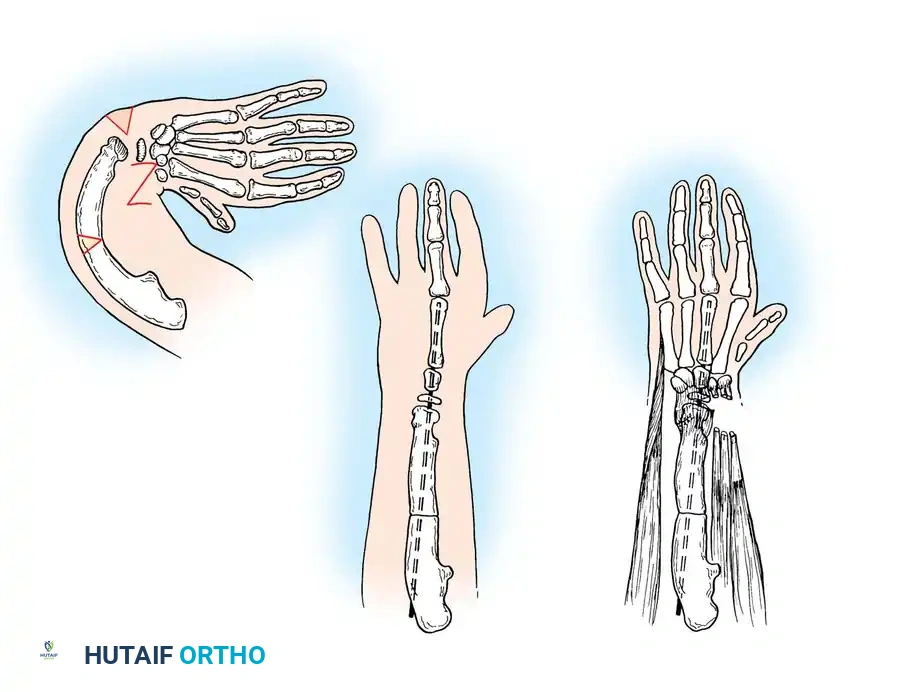

Growth and differentiation proceed in a strict proximal-to-distal fashion, governed by three primary signaling centers that dictate the three-dimensional spatial orientation of the limb:

- The Apical Ectodermal Ridge (AER): Located at the distal tip of the limb bud, the AER is responsible for proximal-to-distal growth. It secretes Fibroblast Growth Factors (FGFs) that maintain the underlying mesoderm in a highly proliferative state known as the progress zone.

- The Zone of Polarizing Activity (ZPA): Situated in the posterior (postaxial) margin of the limb bud mesoderm, the ZPA controls radioulnar (anterior-posterior) differentiation. The primary morphogen secreted by the ZPA is the Sonic Hedgehog (SHH) protein. Disruptions in SHH signaling explain the clinical phenomenon where ulnar-deficient limbs frequently present with associated preaxial (radial) hand deficiencies.

- The Wingless-Type (WNT) Signaling Center: Located within the dorsal ectoderm, this center secretes WNT-7a, which induces the expression of LMX1B in the underlying mesoderm, thereby determining the dorsal differentiation of the limb.

Fig. 76-1 Limb bud. The apical ectodermal ridge extends from anterior to posterior along the dorsal/ventral boundary of the growing limb bud. Proximal to the AER is the progress zone. Within the posterior mesoderm is the zone of polarizing activity. These centers are highly interconnected; limb patterning and growth depend entirely on their coordinated function.

By day 31 of gestation, the hand paddle becomes morphologically distinct. Through a genetically programmed process of cellular apoptosis (programmed cell death), the fissuring of the hand paddle is completed by day 36. The central rays form first, followed rapidly by the preaxial and postaxial digits. The formation of chondral elements, endochondral ossification, and the subsequent development of joints, musculature, and vascular networks follow in rapid succession. The entire embryological formation of the upper extremity is completed by the end of the 8th week of gestation.